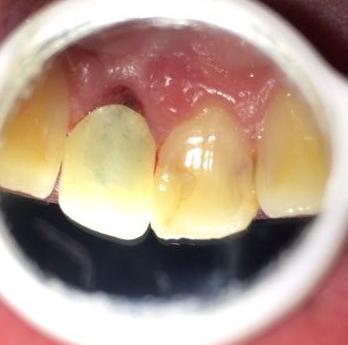

顾名思义,“根面龋”指的是发生在牙根的龋齿。一般情况下,牙根是被牙龈包住形成一种保护的。但人们随着年龄的增大,会出现生理性的牙龈退缩,牙根部位开始暴露。而相对于牙冠来说,牙根部位缺少了牙釉质的保护,所以硬度会相对较低,且容易附着牙菌斑,不容易清洁,更加容易发生龋坏。

很多人发现根面龋是因为日常吃东西时感到经常塞牙或者“刮舌头”,去看牙医通过检查口内、拍牙片才得知,这时候一般根面龋已经形成了一个大龋洞了。若不及时治疗,将会形成牙髓炎,严重者牙根会折断。